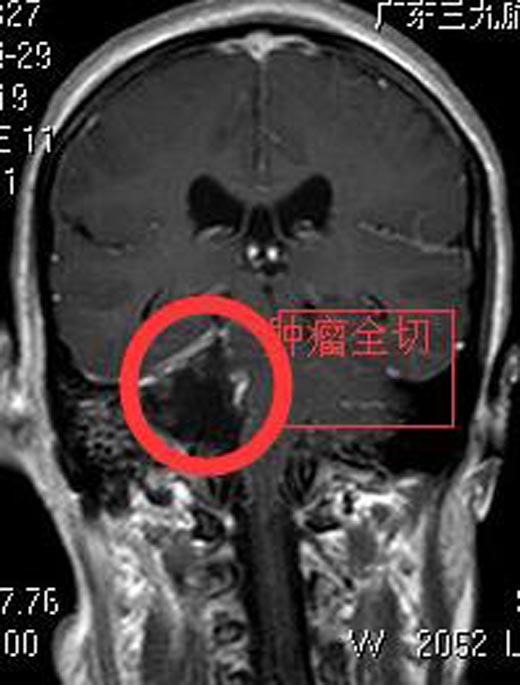

张女士了解病情及治疗方案后,积极要求手术治疗。由综合神经外科鲁明主任主刀,在全麻下行右侧桥小脑角区肿瘤切除术。术中见肉红色肿瘤组织,包膜完整,被小脑前下动脉包绕,质中,血供丰富。显微镜下分块切除肿瘤及大部瘤膜,肿瘤上至三叉神经,下达末组颅神经,与面听神经及脑干明显粘连。切除肿瘤大小约4cm×4cm×3cm,相邻神经、血管解剖保护满意,面听神经解剖保留,手术顺利。术后张女士无后组颅神经损害症状,已康复出院。病理提示:神经鞘瘤。